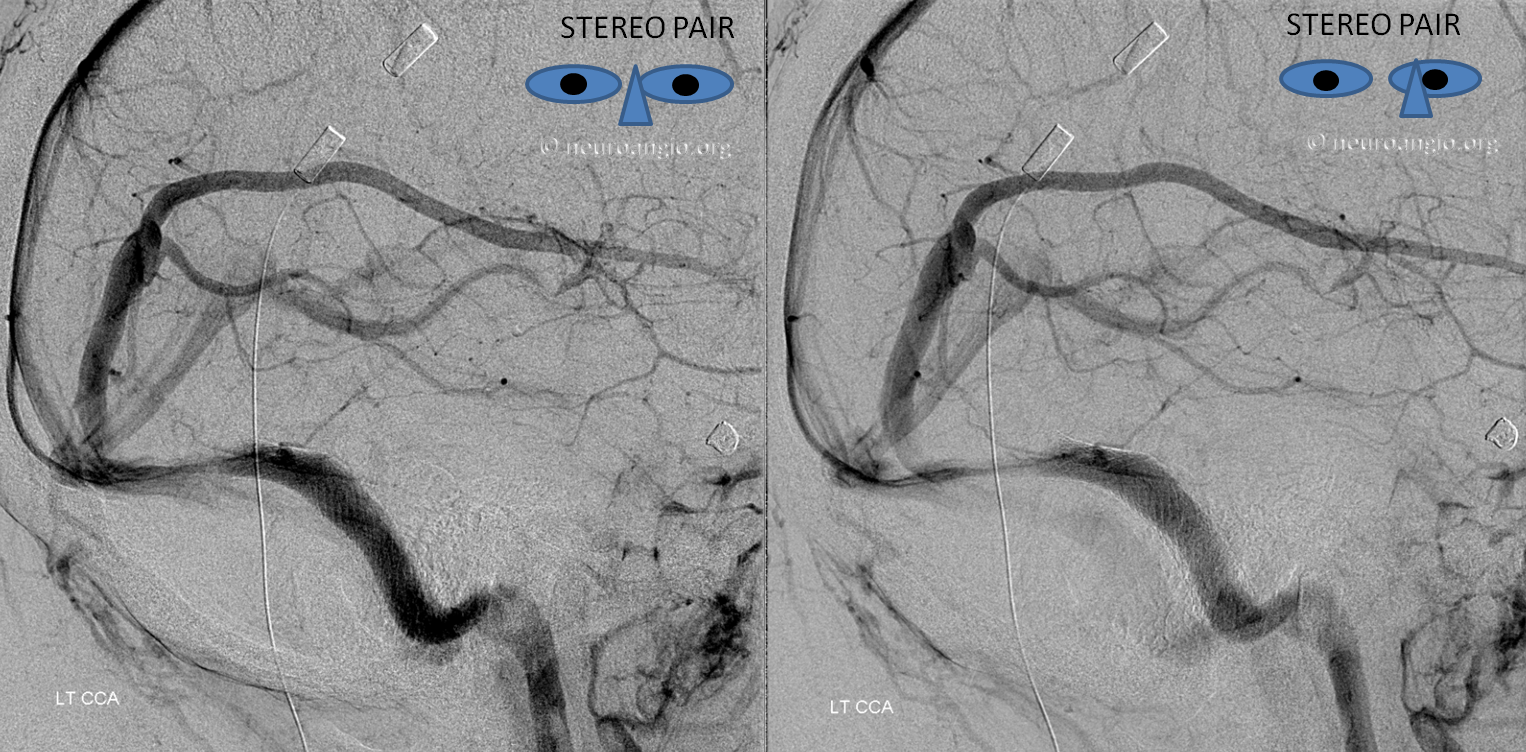

Stereo views of the same arrangement, several years later.

Cinematic Rendering — a very cool visualization algorithm — courtesy Dr. Matthew Young

A stent (yellow) has been placed into the dominant sigmoid sinus. While pulsatile tinnitus was cured, the headaches which initially improved then recurred, and a shunt was eventually placed (purple, white). Notice recurrence of narrowing (black) just distal to the stent, as is typical in such failed stent cases.